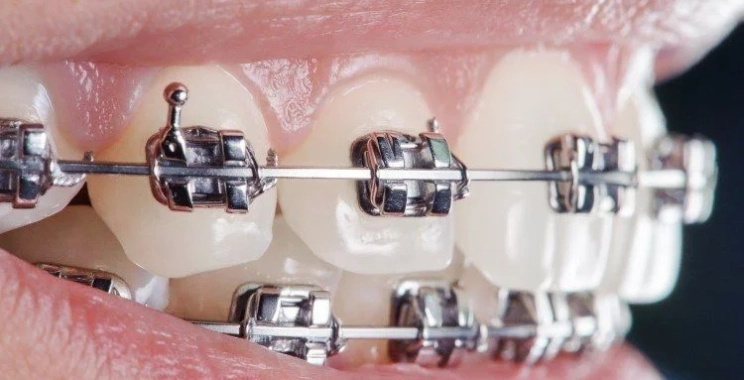

تقويم الاسنان المتزاحمة

يعتبر تركيب تقويم الأسنان أحد أبرز الوسائل العلاجية التي يعتمد عليها الأطباء في مجمع الطب المتميز لعلاج مشكلات الأسنان المتنوعة.

ولقد انتشر بأشكال وأنواع مختلفة بعد أن أثبت فعاليته وكفاءته وأهميته في جعل المرضى يحصلون على الابتسامة التي يرغبون بها بعد عدة أشهر

يمكن أن يساهم التقويم المتحرك أو الثابت في تصحيح وضعية اسنان متراكمه في حالة الازدحام. وهناك بعض الأنواع التي يمكن اللجوء إليها بشكل خاص وهي المعدني والشفاف والخزفي.